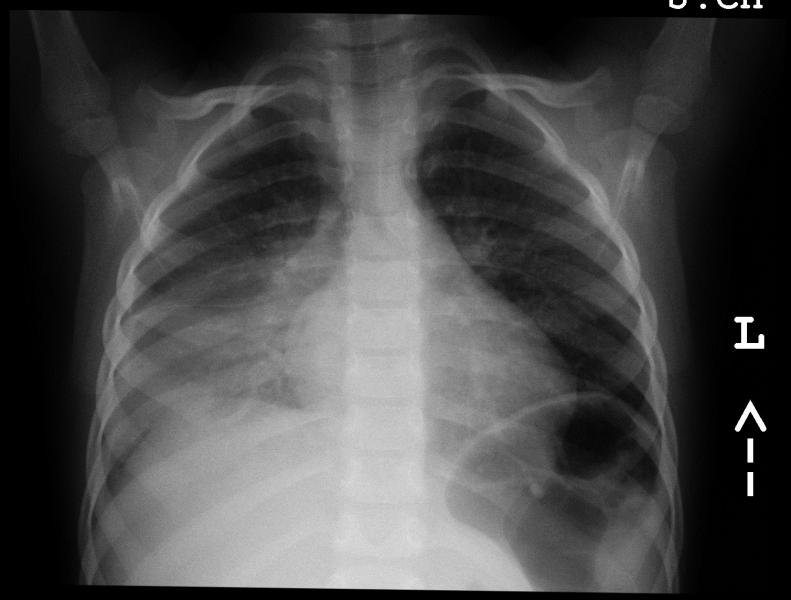

Przypadek 14: 4,5-letni chłopiec skierowany z POZ z podejrzeniem prawostronnego zapalenia płuc. W wywiadzie narastająca gorączka od 4 dni. W badaniu przedmiotowym stwierdzono stłumienie odgłosu opukowego i ściszenie szmeru pęcherzykowego po stronie prawej, oraz wysokie wykładniki stanu zapalnego w badaniach laboratoryjnych.

Rozpoznanie: W badaniu RTG klatki piersiowej stwierdzono zagęszczenia miąższowe w polu środkowym i dolnym płuca prawego z towarzyszącym płynem w prawej jamie opłucnej (warstwa przy bocznej ścianie w dole płuca). Płuco lewe bez zagęszczeń, lewa jama opłucnowa wolna.